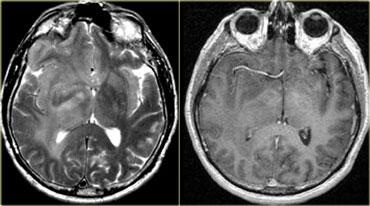

TRÁI: Di căn não. PHẢI: Nhiều u màng não và u thần kinh bao ở bệnh nhân U xơ thần kinh type II (Neurofibromatosis II)

Bệnh đa ổ

Nhiều khối u trong não thường gợi ý bệnh di căn (hình minh họa).

Các u não nguyên phát thường gặp ở một vùng duy nhất, nhưng một số u não như u lympho, u nguyên bào đa hình đa trung tâm (multicentric GBM) và u thần kinh đệm lan tỏa não (gliomatosis cerebri) có thể đa ổ.

Một số khối u có thể đa ổ do di căn gieo rắc: điều này có thể xảy ra trong u nguyên tủy bào (PNET-MB), u màng nội tủy (ependymoma), u nguyên bào đa hình (GBM) và u tế bào ít nhánh (oligodendroglioma).

U màng não và u thần kinh bao có thể xuất hiện nhiều ổ, đặc biệt trong bệnh u xơ thần kinh type II.